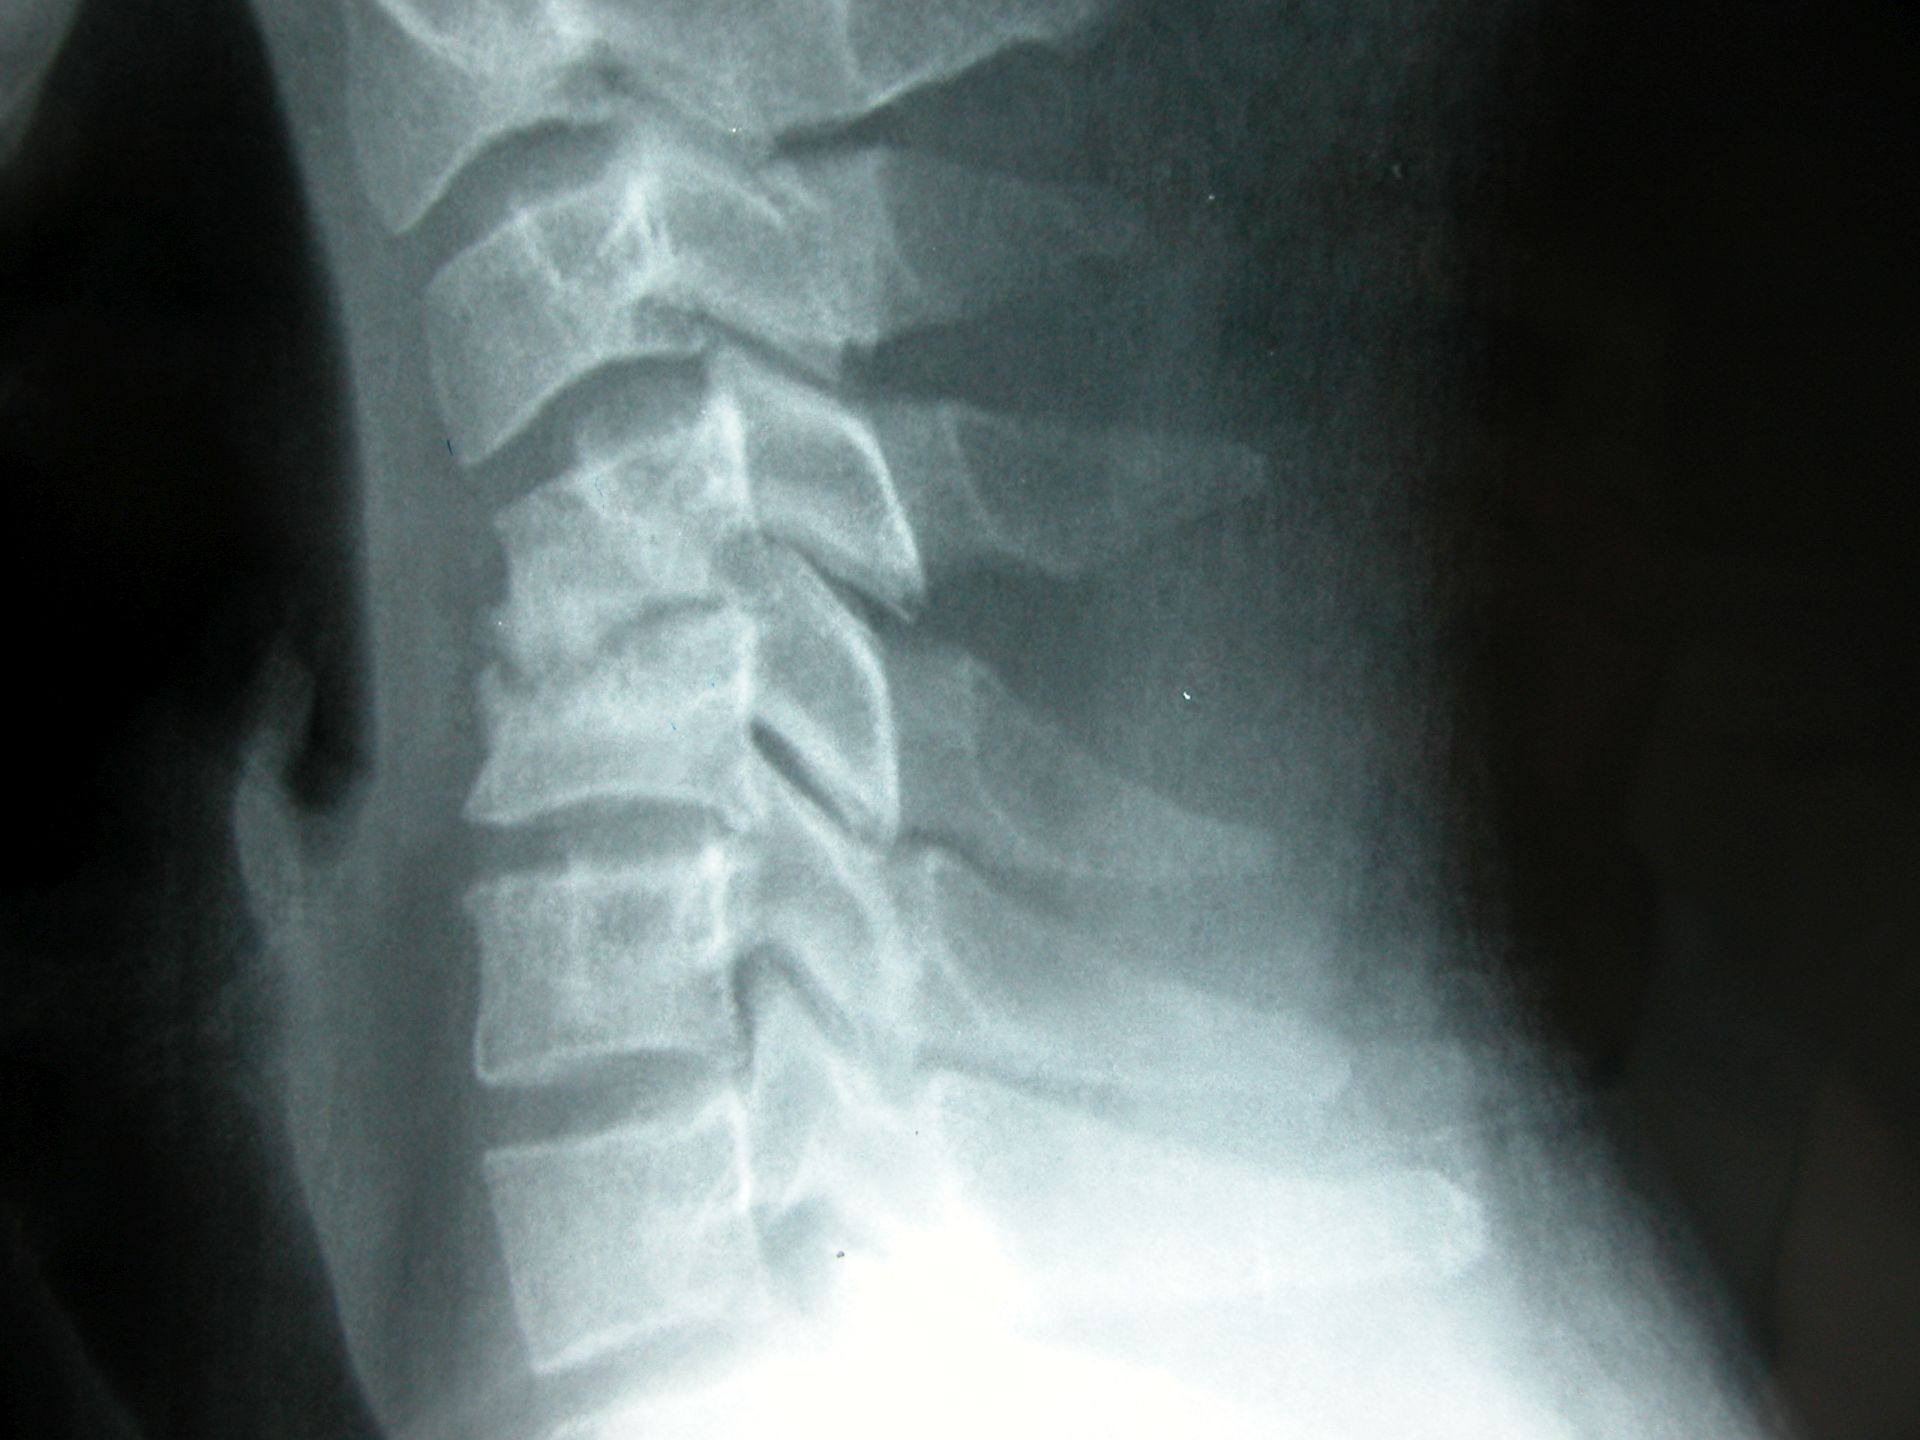

POSTOPERATIVE CARE Άνοιγμα ΕΓΧΥΣΕΙΣ ΜΥΟΣΚΕΛ/ΚΟΥ Άνοιγμα ΚΑΚΩΣΕΙΣ ΑΜΣΣ Άνοιγμα ΚΑΚΩΣΕΙΣ ΟΣΦΥΟΠΥΕΛΙΚΗΣ ΠΕΡΙΟΧΗΣ Άνοιγμα